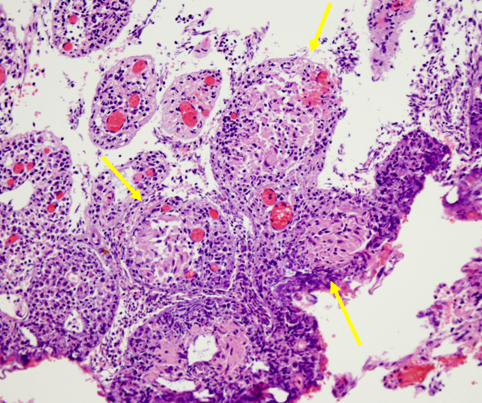

M. giunge alla nostra attenzione, all'et� di 7 anni, per la prima volta al cospetto del nostro allergologo: il suo problema infatti � quel gonfiore �rosso� a carico della labbra e gengive (soprattutto superiori), che interessa anche le guance, il mento e la regione peri-orbitale. Il collega descrive il quadro come una vera e propria ipertrofia da �infiltrazione� (edematosa ed eritematosa) delle gengive e delle labbra, che appaiono fissurate (mai cheilite), con cute arrossata e discheratosica al volto. Trattasi di granulomatosi orofacciale quadro clinico confermato anche dalla biopsia orale.

I genitori raccontano che le hanno gi� tentate tutte (terapia antibiotiche, antimicotiche, anti-infiammatorie) senza ottenere alcun beneficio. L'allergologo allora chiede se la manifestazione appaia correlata all'ingestione di qualche alimento e la madre riferisce che �s�, dottore, sembra esserci una correlazione con il latte, sa M. � un grande bevitore di latte (presenta RAST per latte e uovo positivi), ma l'associazione vale solo per l'edema, mentre l'ipertrofia sembra assolutamente indipendente, perch� persiste nonostante l'alimento non venga assunto�. Il ragazzo non presenta alcun altro segno e sintomo associato: non perdita di peso (anzi � in soprappeso), non febbre, non disturbi gastrointestinali di alcun genere. Gli accertamenti ematochimici mostrano un emocromo nella norma, negativit� degli indici di flogosi (VES 6 e PCR negativa) e delle IgG (1257), ASCA e ANCA negativi, non deficit del C1q esterasi inibitore, negative Mantoux e coprocolture, calcemia e ACE sierica nella norma, normali le sottopopolazioni linfocitarie. Vengono eseguiti anche test di funzionalit� intestinale al doppio zucchero (lattulosio/ramnosio) che dimostra un aumento patologico della permeabilit� alle macromolecole (rapporto L/M 0.049 v.n. <0.026) e il dosaggio della calprotectina fecale (indicatore altamente sensibile di flogosi intestinale) che risulta invece assente. Considerata la possibile associazione tra morbo di Crohn e granulomatosi oro-facciale viene eseguita una gastroscopia, una colonscopia con biopsie e una ileoscopia con videocapsula che mostrano un quadro di duodenite cronica di grado lieve, con una mucosa duodenale con aspetti di iperplasia follicolare linfoide (soprattutto dell'ileo terminale e valvola ileo-ciecale) e una colite afosa ad impronta eosinofila. Pertanto, l'aumento della permeabilit� intestinale associata all'esito dell'esame istologico orientano fortemente verso una genesi allergica della granulamatosi orofacciale e quindi avviamo una dieta di esclusione per latte, uovo e derivati. A un mese dall'avvio della dieta il quadro appare notevolmente migliorato, seppur la risposta alla dieta sia in realt� parziale: scomparsa dell'edema labiale e gengivale, persistenza invece dell'infiltrato duro e parenchimatoso al labbro superiore e gengiva, anche se ridotto. Sempre nella norma l'emocromo e negativi gli indici di flogosi. Il miglioramento clinico, nonostante l'assenza di segni di allergia, la presenza di prick e RAST test negativi, ci impone di insistere sulla necessit� di continuare la dieta di esclusione. Tuttavia l'adesione del ragazzo alla dieta non � molto rigorosa: si hanno infatti 2 episodi di riacutizzazione dell'edema labiale in seguito all'ingestione di uova, con presenza di moderata ipereosinofilia periferica (eosinofili 470/mm3) a conferma delle trasgressioni dietetiche (con necessit� di utilizzare steroide a brevi perioidi, con peraltro efficacia). A un anno dalla diagnosi, la dieta di esclusione non aveva portato ad alcun miglioramento clinico, anzi nonostante un'adesione rigorosa (questa volta!), si era assistito a un franco peggioramento: labbra edematose, fissurate, la mucosa gengivale tumefatta, che impedivano al ragazzino perfino di sorridere. Cute perianale arrossata, con piccola ulcera interglutea. All'emocromo persisteva un' eosinofilia periferica, ma era presenta anche lieve anemia (Hb 11 g/dl con MCV 76), ipoferritinemia (10.85), ulteriore aumento della permeabilit� al test al doppio zucchero (0.079) e positivizzazione della calprotectina fecale (58 mg/kg), lieve aumento della VES (32), positivizzazione dei c-ANCA e negativi apparivano i patch-test per gli allergeni maggiormente implicati nella granulomatosi oro-facciale (cannella e sodiobenzoato). Questi nuovi reperti ci imponevano quindi di rivalutare completamente la malattia anche dal punto di vista endoscopico e istologico. In corrispondenza del retto, sigma e colon discendente erano presenti papule rilevate ulcerate al centro e piccole afte diffuse, a livello ileale distale la mucosa appariva granulare ma senza lesioni ulcero-erosive. Il risultato istologico delle biopsie coliche dimostrava la presenza di infiltrato cronico transmucoso con presenza di granulomi, quadro compatibile con il morbo di Crohn.